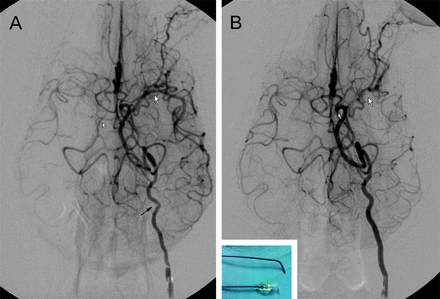

The beagle dog's cerebral ischemic models were established through the use of a method similar to the one used in our previous reports.9,10 Briefly, a prepared autologous clot (approximately 1.7 mm in diameter and 5 mm in length) was injected into the left proximal MCA under live fluoroscopy, and embolization was confirmed by angiography. After that, a 5F catheter was guided to 2 cm distal to the orifice of the ipsilateral ICA to block the blood flow for 2 hours. The animals were then transported to the MR imaging suite for imaging studies.

All 20 cerebral ischemic models were established successfully without any procedure-related complications or casualties (Fig 1). DWI+ lesions were seen in all 20 beagle dogs starting from 3 hours after embolization. The DWI indicated that the cerebral ischemic lesions were located on the ipsilateral caudate nucleus and the cortical area of the temporal lobe. Generally, the ischemic lesions were first found at the caudate nucleus, followed by the lesions located in the cortical area of the temporal lobe (Fig 2).

Representative real-time DSA images before and after MCA embolization in beagle dogs. A, Angiography clearly demonstrated the anatomy of intracranial arteries, including the left MCA trunk (large arrowhead), tortuous ICA (black arrowhead), and cerebral circulation (small arrowhead) through the left ICA injection before embolization. B, At the arterial phase, angiography immediately after thrombus injection through the catheter, the main trunk of MCA was completely occluded (small and large arrowheads). After that, a 5F catheter was guided to 2 cm distal to the orifice of ipsilateral ICA to block the blood flow for 2 hours. The catheter used in our study is displayed in left-bottom inset.